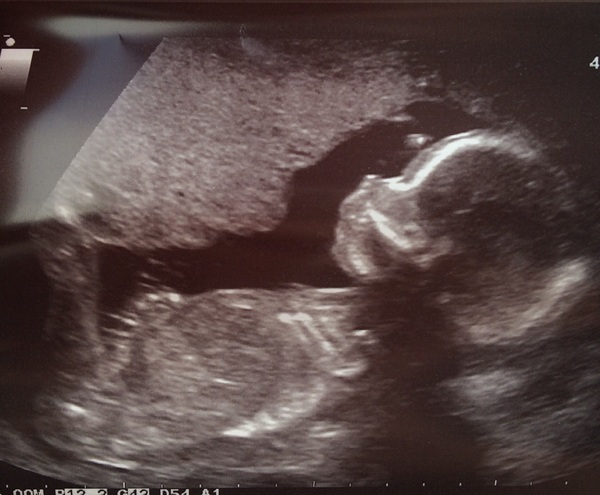

IfAtFirstUDontSucceed · 22/09/2016 07:34

Oops forgot to attach scan. Our little ... Girl??

Ifatfirst congrats!!! What a cutie Smile

Congrats ifatfirst looks like a wee girl to me 😀

Congrats ifatfirst! I think with a girl they often can't be 100% certain. With a boy you can usually be more sure, there was definitely no ambiguity in our scan!